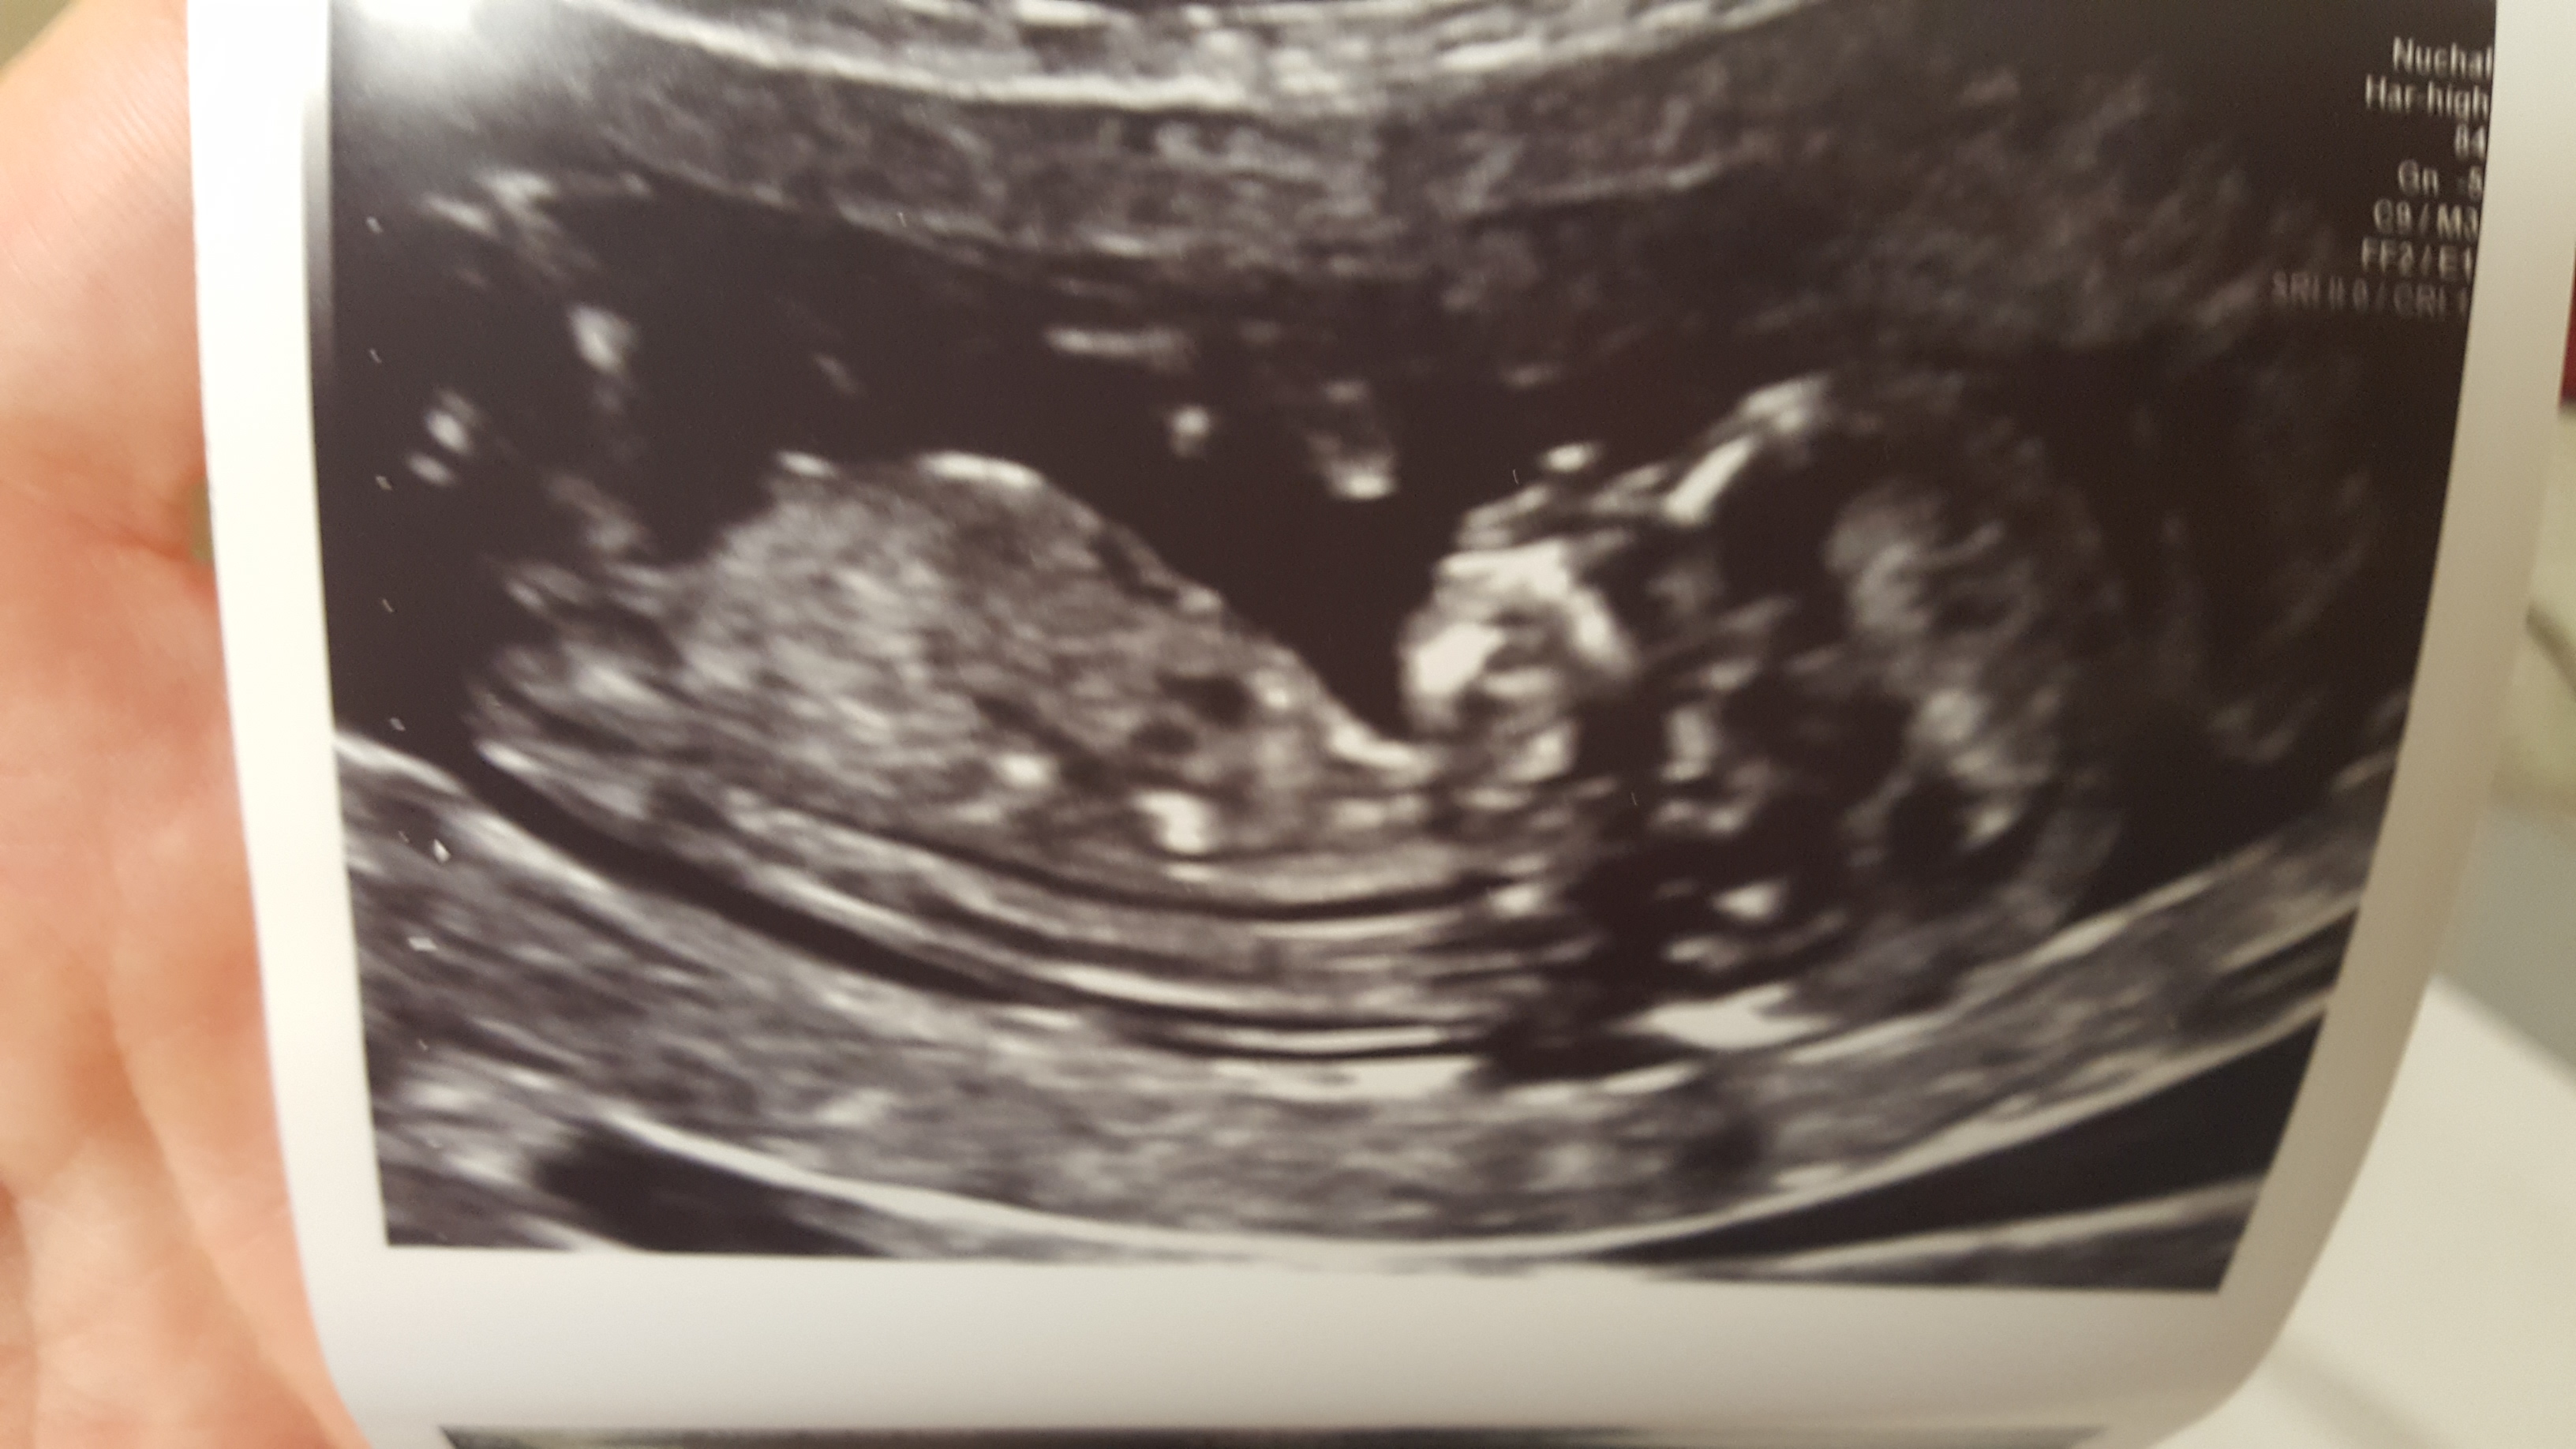

Any other side profile pics?

Girl lean from the last pic. Not terribly confident though- I'd say 60/40.

Thank you. The nub seems to be pointing downwards which confused me but I leaning pink

Pink guess x

I'm going boy as that looks like stacking in the first two pictures, only 60:40 to blue though...